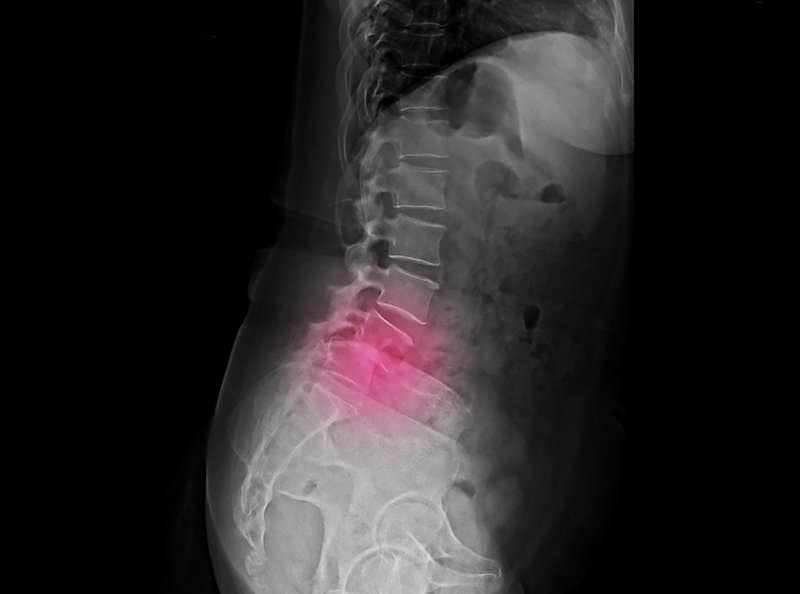

A herniated disc is a bulge or tear in the ligament that connects two vertebrae in the spine. This injury usually occurs as a result of an injury or degenerative disc disease caused by the aging process. The herniated disc will cause pressure on spinal nerves causing pain. Discomfort can range from mild to severe pain and may last for weeks or months.

Common treatments include physical therapy, pain medication, and steroid injections. While these treatment options among others are excellent options it is best to avoid this type of injury in the first place.

Treatment Options

These recommendations will aid you in preventing herniated discs. Still, there is always a risk that they will occur. If you find yourself suffering from a herniated disc there a many treatment options available to you. Nonsurgical treatment options include: